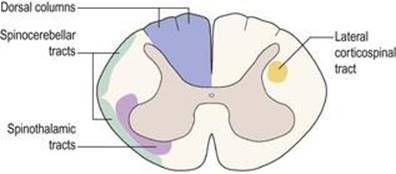

نخاع ساختاری نسبتاً تمایز نیافته در مقایسه با مغز است. در نتیجه، اصول اساسی سازمان، که در اوایل رشد جنینی ایجاد شده است، میتواند به آسانی حتی در بند ناف انسان بالغ شناسایی شود (شکل ۱.۱۶). طناب نخاعی تقریباً استوانه ای شکل است که در مرکز آن یک کانال مرکزی وستیژیال قرار دارد. جداسازی اجسام سلولی از رشتههای عصبی، شکل مشخصه «H» یا «پروانه» را به هسته مرکزی ماده خاکستری که کانال مرکزی را احاطه کرده است میدهد. چهار امتداد ماده خاکستری مرکزی به صورت پشتی و بطنی به سمت خطوط اتصال ریشههای پشتی و شکمیاعصاب نخاعی پیش میروند. اینها به نام شاخ پشتی و شاخ شکمیشناخته میشوند، به ترتیب. شاخ پشتی محل خاتمه بسیاری از نورونهای آوران است که تکانههای گیرندههای حسی را در سراسر بدن منتقل میکند و محل منشأ مسیرهای صعودی است که تکانههای حسی را به مغز منتقل میکنند. شاخ شکمیحاوی نورونهای حرکتی است که عضله اسکلتی را عصب دهی میکند. علاوه بر این، تنها در سطوح قفسه سینه و کمری فوقانی بند ناف، مجموعه دیگری از اجسام سلولی کوچکتر شامل شاخ جانبی است که حاوی نورونهای پیش گانگلیونی متعلق به بخش سمپاتیک سیستم عصبی خودمختار است.

نخاع از یک هسته مرکزی ماده خاکستری، حاوی اجسام سلولهای عصبی و یک لایه بیرونی ماده سفید یا رشتههای عصبی تشکیل شده است.

در داخل ماده خاکستری، شاخ پشتی حاوی نورونهای حسی، شاخ شکمیحاوی نورونهای حرکتی و شاخ جانبی حاوی نورونهای سمپاتیک پیش گانگلیونی است.

در داخل ماده سفید مسیرهای فیبر عصبی صعودی و نزولی وجود دارد که نخاع را با مغز پیوند میدهد.

مسیرهای صعودی اصلی ستونهای پشتی، مسیرهای اسپینوتالاموس و مجاری نخاعی مخچه هستند. دستگاه قشر نخاعی یک مسیر نزولی مهم است.

محیط بند ناف از ماده سفید تشکیل شده است که شامل رشتههای عصبی درازا میباشد. اینها به یک سری از مسیرهای صعودی سازماندهی میشوند که اطلاعات را از تنه و اندامها به مغز میرسانند، و مسیرهای نزولی که توسط آنها مغز فعالیتهای نورونهای نخاع را کنترل میکند (شکل ۱.۱۷). مسیرهای صعودی اصلی ستونهای پشتی (fasciculus gracilis و fasciculus cuneatus) هستند که لمس ظریف و حس عمقی را حمل میکنند، مجاری اسپینوتالاموس که حامل درد، دما، لمس و فشار درشت هستند، و مجاری نخاعی مخچه ای هستند.که اطلاعات را از گیرندههای عضلانی و مفصلی به مخچه منتقل میکند. در میان مسیرهای نزولی، یکی از مهمترین آنها، دستگاه قشر نخاعی جانبی است که حرکات ارادی ماهرانه را کنترل میکند.

شکل ۱.۱۷ مقطع عرضی از طناب نخاعی که محل مسیرهای فیبر عصبی اصلی صعودی (سمت چپ) و نزولی (سمت راست) را نشان میدهد.

شکل ۱.۱۷ مقطع عرضی از طناب نخاعی که محل مسیرهای فیبر عصبی اصلی صعودی (سمت چپ) و نزولی (سمت راست) را نشان میدهد.

مسیرهای حسی اصلی

حس در تنه و اندامها از گیرندههای حسی در محیط توسط اعصاب محیطی و ریشههای عصبی به گانگلیونهای ریشه پشتی و سپس به نخاع هدایت میشود. در داخل نخاع یک واگرایی از مسیرهای حسی وجود دارد که دارای روشهای حسی مختلف هستند (شکل ۱.۲۴). مسیرهای حسی درد و دما در طناب نخاعی جدا میشوند و در مجرای اسپینوتالاموس طرف مقابل بالا میروند تا به تالاموس و از آنجا به قشر حسی طرف مقابل نیمکره مغز برسند. در مقابل، مسیرهای لمسی و حس عمقی در ستونهای پشتی (خلفی) نخاع، قبل از اینکه در ساقه تحتانی مغز جدا شوند و از طریق تالاموس به قشر حسی طرف مقابل عبور کنند، بالا میروند.

ضایعات یک طرفه نخاع یا ساقه تحتانی مغز منجر به از دست دادن حس جدا میشود.

ضایعات ساقه فوقانی مغز یا نیمکره مغز منجر به از دست دادن تمام حس در سمت مقابل بدن میشود.

این آرایش متفاوت به ضایعات نخاع و ساقه مغز اجازه میدهد تا ترجیحاً به یک مسیر آسیب برساند و مسیر دیگر را حفظ کند. اصطلاح از دست دادن حسی تفکیک شده به یافتههای بالینی از دست دادن انتخابی روشهای لمس و حس عمقی، با حفظ مدالیتههای درد و دما و یا بالعکس اشاره دارد. این از دست دادن انتخابی روشهای حسی ناشی از درگیری انتخابی توسط ضایعات مسیرهای عملکردی خاص برای لمس / حس عمقی یا درد / دما است. ضایعه ستونهای پشتی طناب نخاعی منجر به از دست دادن حس حس عمقی یا لمس همان طرف در زیر سطح ضایعه میشود. در مقابل، ضایعه دستگاه اسپینوتالاموس منجر به از دست دادن درد/دمای پایین تر از سطح ضایعه میشود.

به عنوان مثال، ضایعه یک طرفه نخاع قفسه سینه منجر به از دست دادن حس لامسه و حس عمقی همان طرف و از دست دادن احساس درد و دمای طرف مقابل در تنه و اندام تحتانی زیر سطح ضایعه میشود. علاوه بر این، همانطور که در زیر توضیح داده شد، یک”ضعف هرمی”همان طرف در اندام تحتانی وجود دارد. در مجموع، اینها به عنوان همیکورد یا سندرم براون سکوارد شناخته میشوند ( شکل ۸.21E را ببینید).